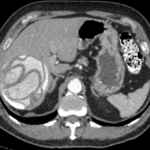

El diagnóstico se basa en hallazgos clínicos, serológicos y de imágenes. La ecografía tiene una sensibilidad del 90-95% (Silva et al., 2006), mientras que la tomografía computada (TC) y la resonancia magnética (RM) ofrecen mayor especificidad anatómica para definir número, ubicación y complicaciones, así como para caracterizar la extensión extrahepática (Maeda et al., 2021; Singh et al., 2001). El realce de contraste suele ser escaso o nulo, reflejando la baja vascularidad de la lesión (Patnana et al., 2018).

- Órgano afectado: hígado: 146 (90,7%); pulmón: 5; bazo: 5; riñón: 3; vesícula: 1; estómago: 1.

- Clasificación de Gharbi: tipo I: 16,4%; tipo II: 11%; tipo III: 6,8%; tipo IV: 13,7%; tipo V: 52,1% (calcificados).

La alta proporción de quistes calcificados (fase inactiva) sugiere que muchos casos permanecieron asintomáticos durante años y fueron diagnosticados tardíamente. Esto refuerza la hipótesis de que la hidatidosis puede estar siendo subdiagnosticada en la región, dado que la zona es altamente endémica y la enfermedad suele pasar inadvertida hasta fases avanzadas.